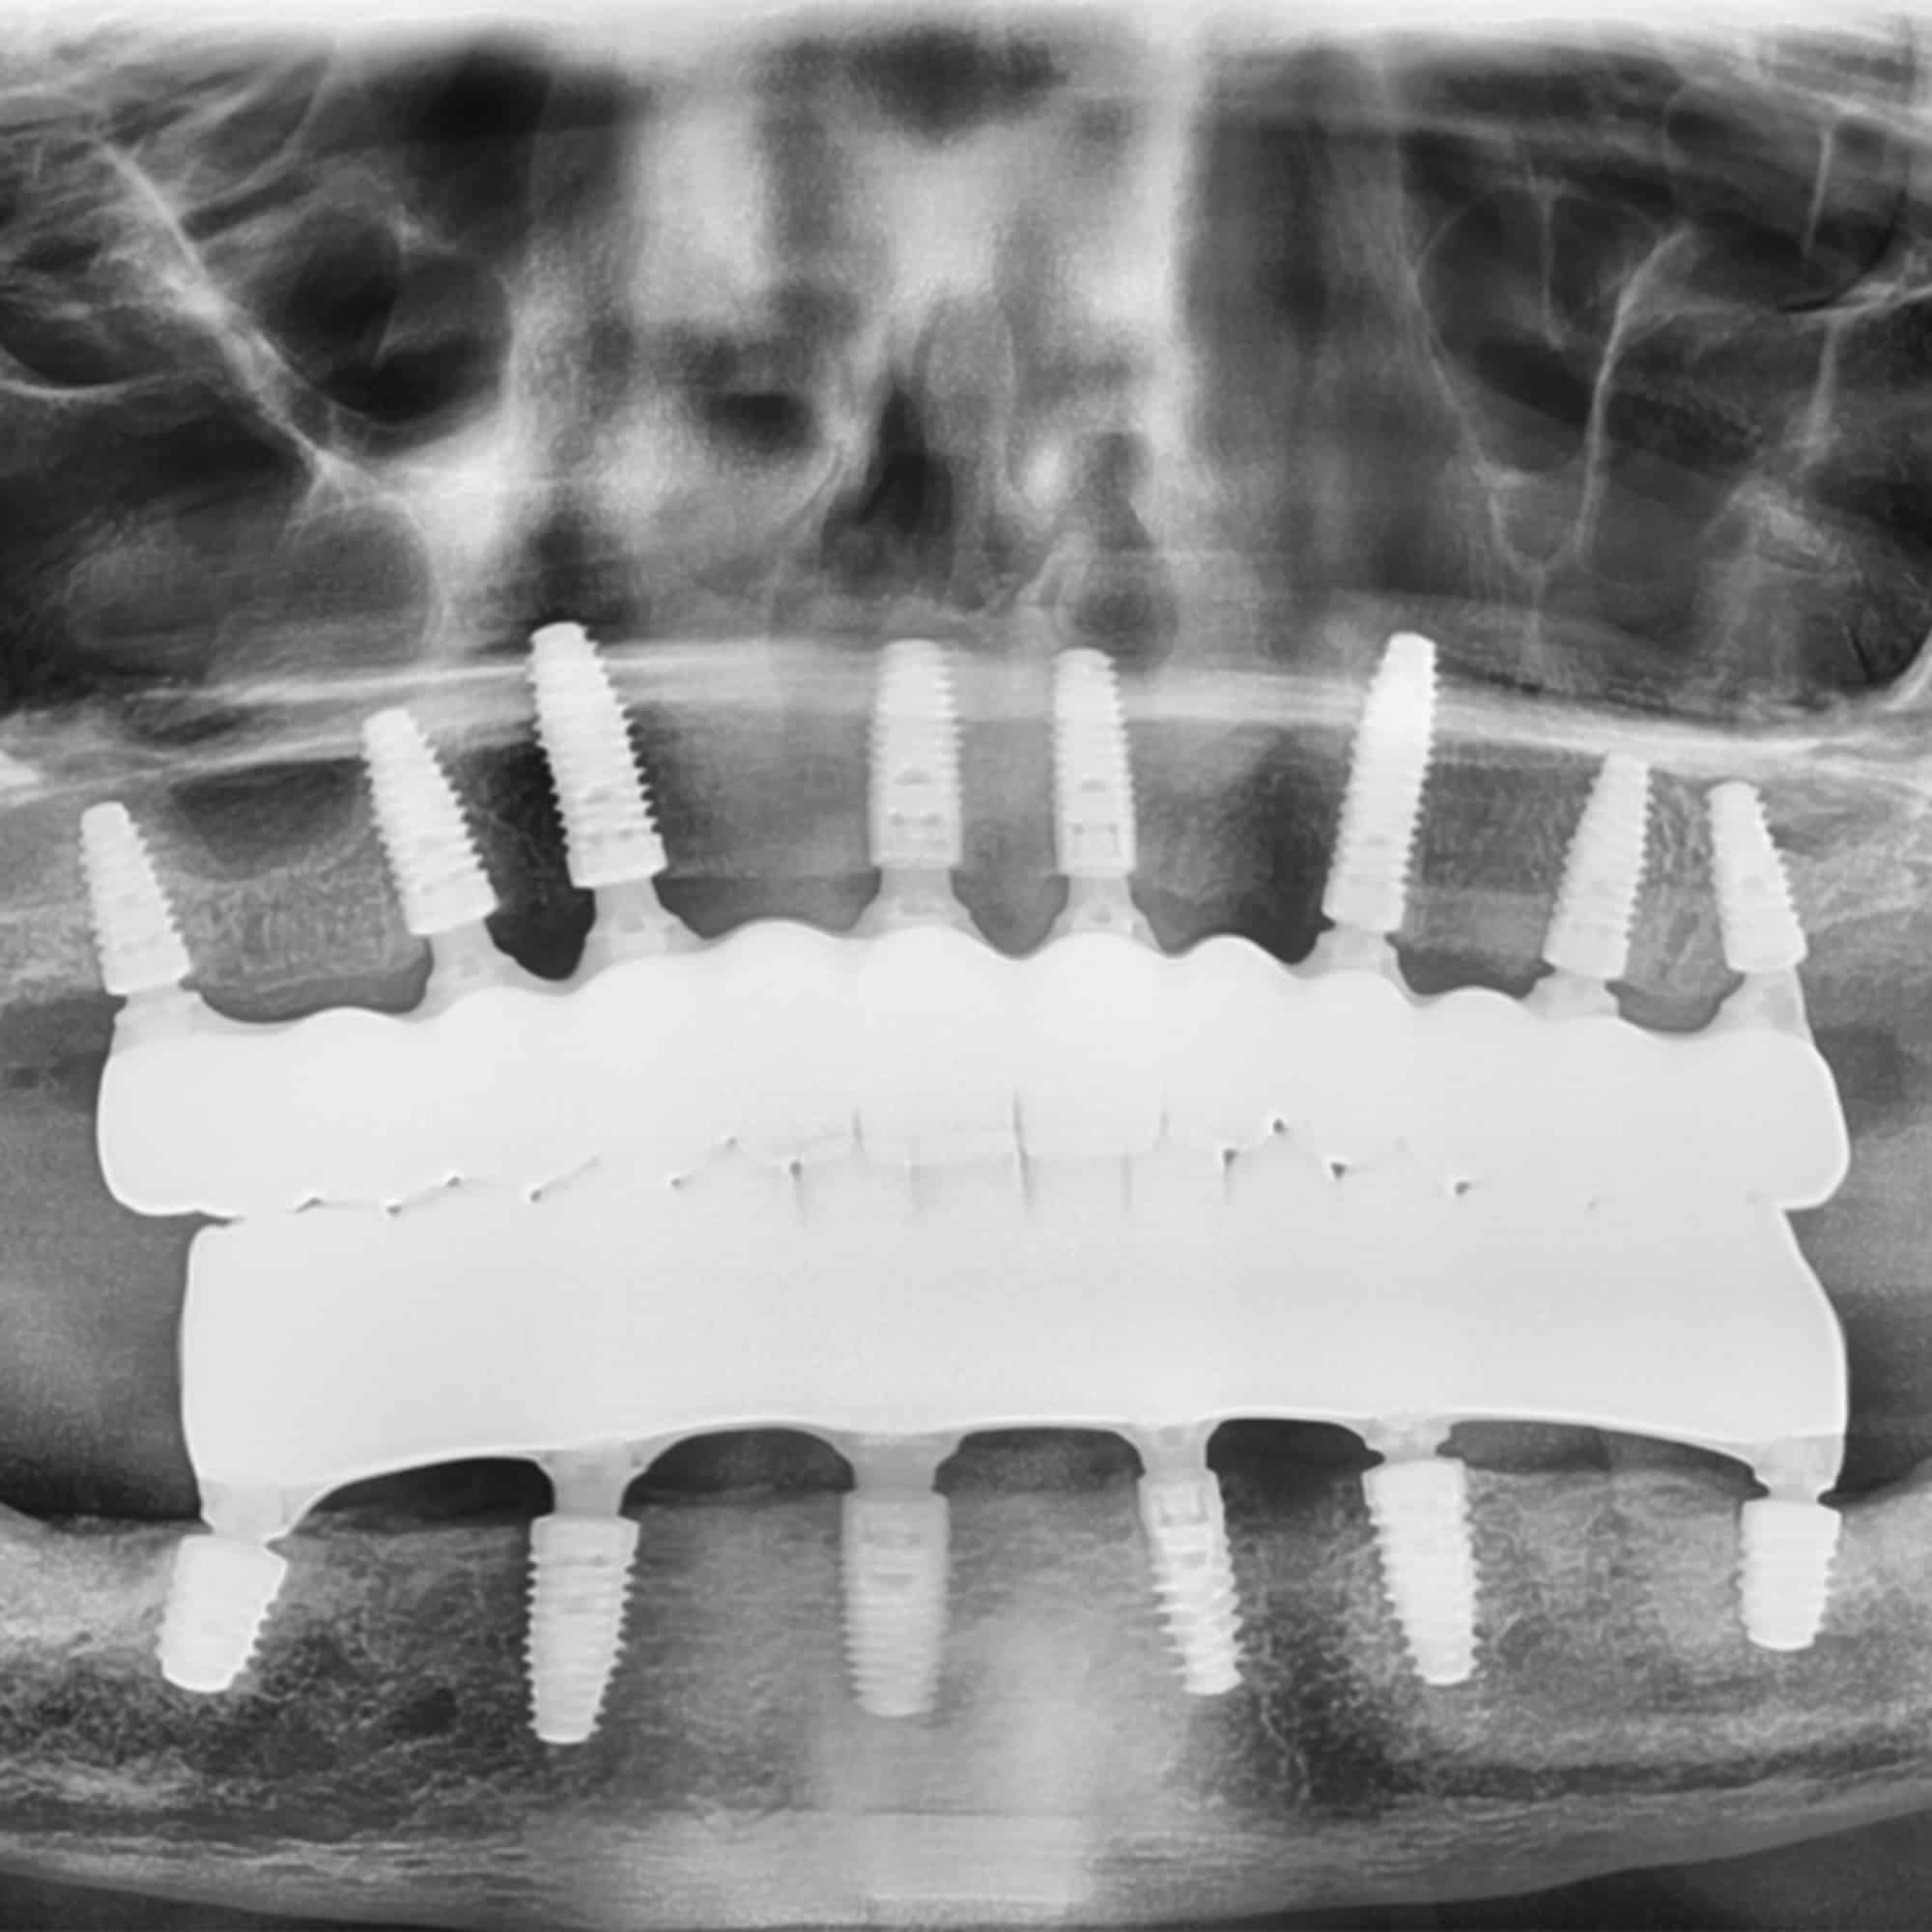

The Anatomy of Full Mouth Dental Implants

Full mouth dental implants typically include:

- Titanium Implants

Placed by your oral and maxillofacial surgeon in your jawbones, the titanium implants serve as permanent anchors for your prosthesis (artificial teeth) - Abutments

Small connectors that secure the prosthetic teeth to the implants - Prosthetic Arches

Completely realistic, durable sets of teeth custom crafted by a specialized prosthodontist. Arches can be permanently fixed to your implants for convenience or removeable like snap on dentures.

This three-part system creates a foundation that looks natural, feels secure, and stands the test of time.